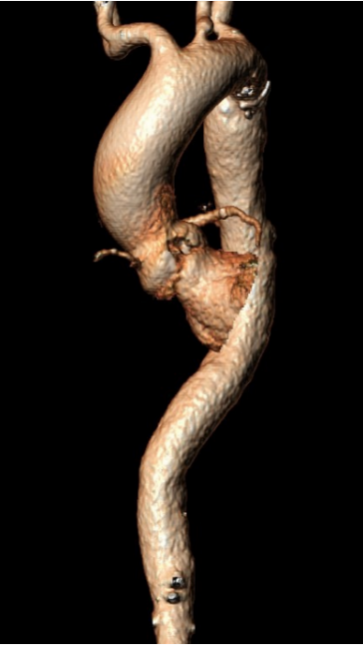

3.近主动脉弓处降主大弯侧血肿,器械通过需避开对此区域的压迫;

手术策略采用右侧股动脉为主入路,全麻配合食道超声进行。根据瓣环测量数据,初步确定选择Evolut PRO 29mm瓣膜。是否需要针对Type0型二叶瓣采用downsize策略,团队进行了详尽探讨,决定先行20mm球囊扩张,根据球囊形态和瓣周漏情况决定最终选型。

Evolut PRO 的递送系统对入路要求小,顺应性出色,装载瓣膜后仍能良好地顺应工作导丝形态,有效避免了对该患者降主动脉水肿部位的压迫,轻松抵达释放位置。

结合术中食道超声可见,Evolut PRO瓣膜与患者自身解剖结构贴合良好,无瓣周漏,跨瓣压差由术前110mm Hg即刻降至10mm Hg,峰值流速由5m/s降至1.8m/s,手术取得圆满成功。